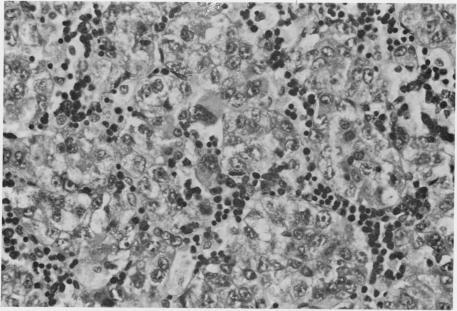

In 9 years in Kenya, 34 examples of primary liver cancer wer diagnosed in patients in the first two decades of life. This represents 4.7% of all liver cancers during this period. The larger proportion (29) were hepatocellular carcinoma. In the second decade, there was a notable association with macronodular cirrhosis. Analogy with experimental work suggests that cells in mitotic cycle may be more vulnerable to the effect of environmental carcinogens. Five examples of hepatoblastoma were identified at ages from 2 months to 14 years; none showed the features of "mixed" tumours. The ratio of hepatoblastoma to hepatocellular carcinoma was the reverse of that found in other large series of juvenile hepatic tumours. The histopathological features of these tumours are described and problems of their classification are discussed.

在肯尼亚的9年里,34例原发性肝癌在20岁之前的患者中被诊断出来。这占该时期所有肝癌的4.7%。其中较大比例(29例)为肝细胞癌。在第二个十年中,与大结节性肝硬化有显著关联。与实验工作的类比表明,处于有丝分裂周期的细胞可能更容易受到环境致癌物的影响。在2个月至14岁的年龄段中发现了5例肝母细胞瘤;均未表现出“混合”肿瘤的特征。肝母细胞瘤与肝细胞癌的比例与其他大量青少年肝脏肿瘤系列中的情况相反。描述了这些肿瘤的组织病理学特征,并讨论了它们的分类问题。